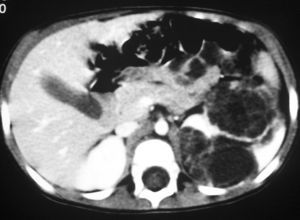

De los pacientes diagnosticados de carcinoma de células renales (n= 4) (con edad y presentación mostrados en la tabla 2) en dos casos se localizaron masas renales en la corteza renal, con infiltración del sistema pielocalicial. De estos dos, uno demostró fuga de contraste del sistema excretor en la radiografía abdominal post-TC con contraste, y el otro invasión de médula con extensión hasta el uréter proximal (fig. 5). En un único caso se apreciaron abundantes calcificaciones grumosas intratumorales dispersas (fig. 6).

Fig. 5. Carcinoma de células renales. (A) Tomografía computarizada abdominal con contraste intravenoso. Corte axial sobre hilios renales. Riñón derecho aumentado de tamaño con discreto retraso de su función. Masa hipodensa central con extensión al sistema colector y escasa captación de contraste. (B) Pielografía ascendente del riñón derecho. En cálices del polo renal superior existe un defecto de repleción junto a dilatación y deformidad por tumoración que ocupa el sistema colector.

Fig. 6. Carcinoma de células renales. Urografía intravenosa que muestra una masa en hemiabdomen izquierdo, con abundantes calcificaciones grumosas dispersas, que desplaza el sistema pieloureteral.

Se cree que se origina de las células epiteliales de los túbulos renales y se reconocen distintos subtipos celulares6,12.

Suele ser más pequeño que el TW al diagnóstico11. En los estudios radiológicos se suele presentar como una masa sólida, infiltrante, con áreas de necrosis, hemorragia, degeneración quística y calcificaciones, que tienden a ser más densas y homogéneas que en el TW e incluso pueden verse en ganglios con afectación metastásica13. Invade localmente con extensión al retroperitoneo y los ganglios linfáticos. Metastatiza de forma más frecuente en los pulmones, el hueso, el hígado y el cerebro1.

En dos de nuestros pacientes, que presentaron hematuria franca, hubo extensión tumoral hacia los cálices y la pelvis renal, así como afectación ganglionar del retroperitoneo. Los dos casos se trataron con nefrectomía con buena evolución.